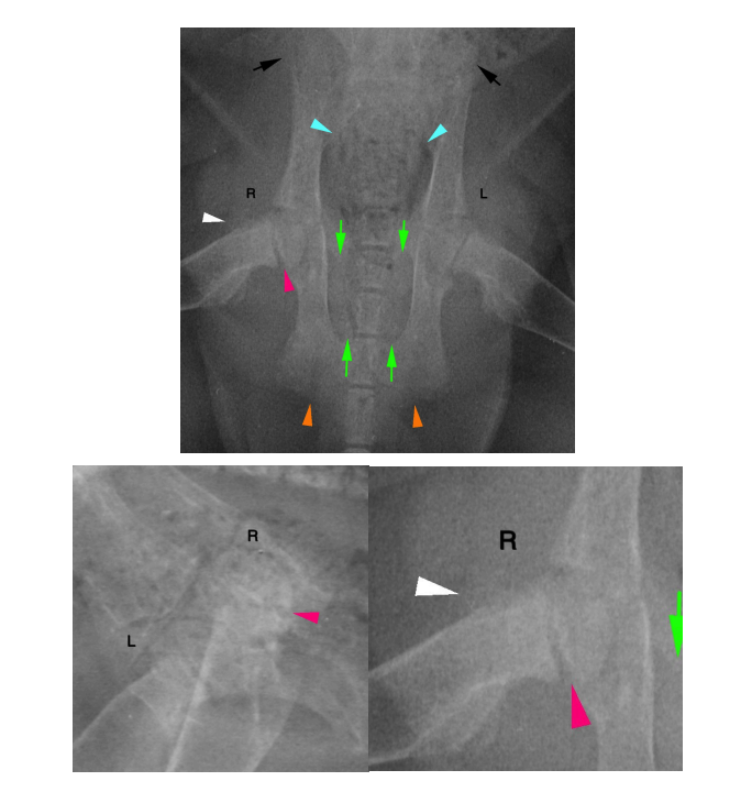

VD image. There is mild increased sclerosis of the right femoral neck as compared to the left.

Additionally, there is faint, thin osseous formation along the cranial margin of the right femoral neck (white arrowhead). On the lateral image, the right proximal physis is indistinct. Increased soft tissue opacity surrounds the left coxofemoral joint.

• Left femoral distal metaphyseal and left tibia/fibular proximal diaphyseal pathological folding fractures

• Wide left proximal femoral physes, likely indicates a capital physeal fracture, with regional soft tissue swelling

• Right tibial proximal metaphyseal periosteal proliferation

• Diffuse osteopenia of the lumbar vertebrae and pelvis, with narrowing of the pelvic canal, as described

The above findings are most consistent with nutritional secondary hyperparathyroidism resulting in osteomalacia from calcium or phosphorus imbalance, (all meat diets). Primary hyperparathyroidism is considered less likely but not excluded. The osseous changes to the right tibia may suggest a prior healing fracture.

An extended leg ventrodorsal image is recommended for evaluation of the right proximal femoral physis to better assess a slipped capital physis. The widened physis does suggest that this is fractured.

Parathyroid hormone and ionized calcium levels may also be considered.